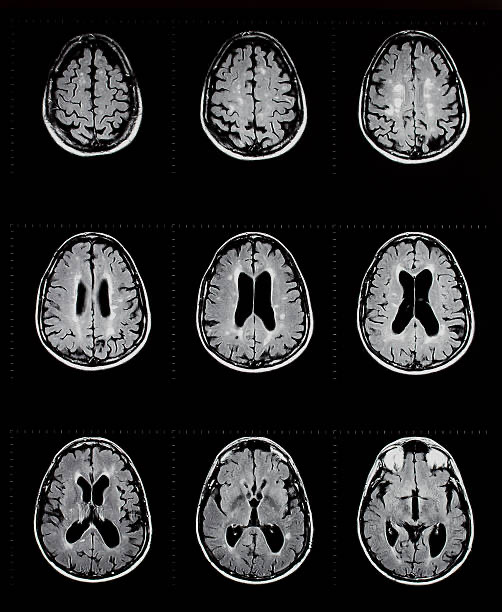

MS’te tanı uzman hekim tarafından MR görüntüleme, beyin omurilik sıvısı (BOS) inceleme ve nörofizyolojik tetkikler yapılarak konur.